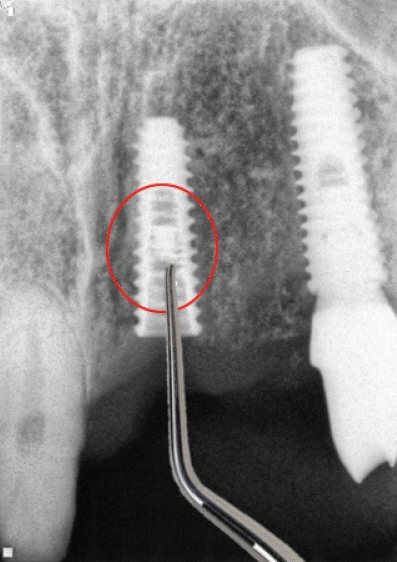

임플란트 보철물의 연결나사나 지대주가 파절된 경우 치주판만을 거상하고 파절편을 제거하는 경우 차97악골내고정용 금속제거술㈜을 산정하며 Bur값은 28,070 원을 적용한다[4]. 치과임플란트는 보철물이 나사와 지대주로 연결되어 있는데 오랜기간 사용되다 보면 조임이 풀라면서 피로파절이 발생되는 경우가 있다. 이를 제거하는 과정이 과거에는 비급여 적용되었으나 2014년 7월 1일 이후로는 악골내고정용금속제거술 등에서 가장 저렴한 술식으로 적용하게 되었다. 이때 다양한 기구가 사용되는데 버값은 (다) 28,070원이 적용된다.이를 위해서는 임플란트 보철제거가 우선인데 보철물제거는 차19치과수복물 또는 보철물의 제거(복잡)를 적용할 수 있다. 치과보험심사평가원에서는 종종 이를 삭감하는 경우가 빈발하니 청구시에 내역을 추가하거나 보철물제거 후 구강내 방사선사진을 촬영하는 것이 추천된다.- 5. 치주외과수술과 치과임플란트 제거술 동시 시행시 수기료 산정방법